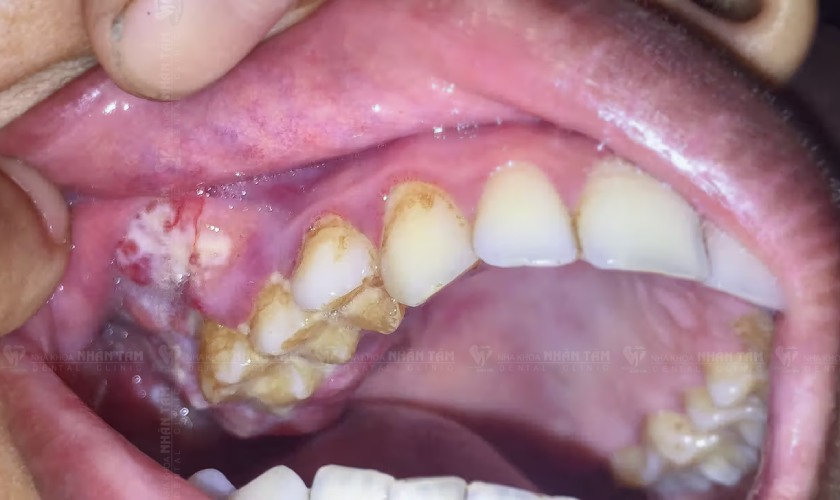

Xuất hiện khối u: Trong thời gian ngắn, các tế bào ung thư phát triển sẽ hình thành khối u ở nướu. Khối u có thể có màu đỏ, trắng và có thể chảy máu. Lúc này bệnh nhân sẽ cảm thấy đau.

Xuất hiện khối u ở nướu